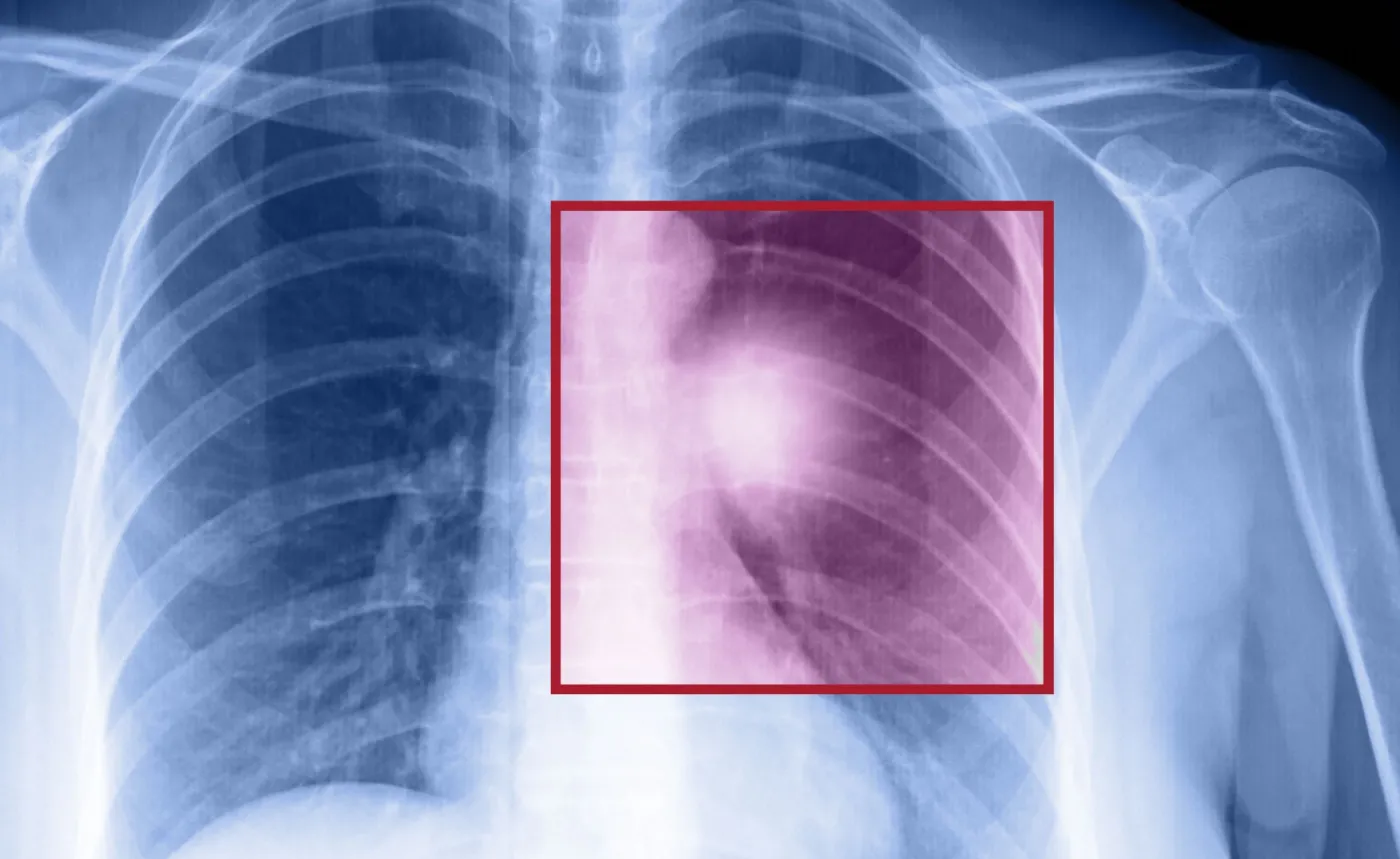

Kobieta chora na nowotwór

Kobieta chora na nowotwór/Shutterstock